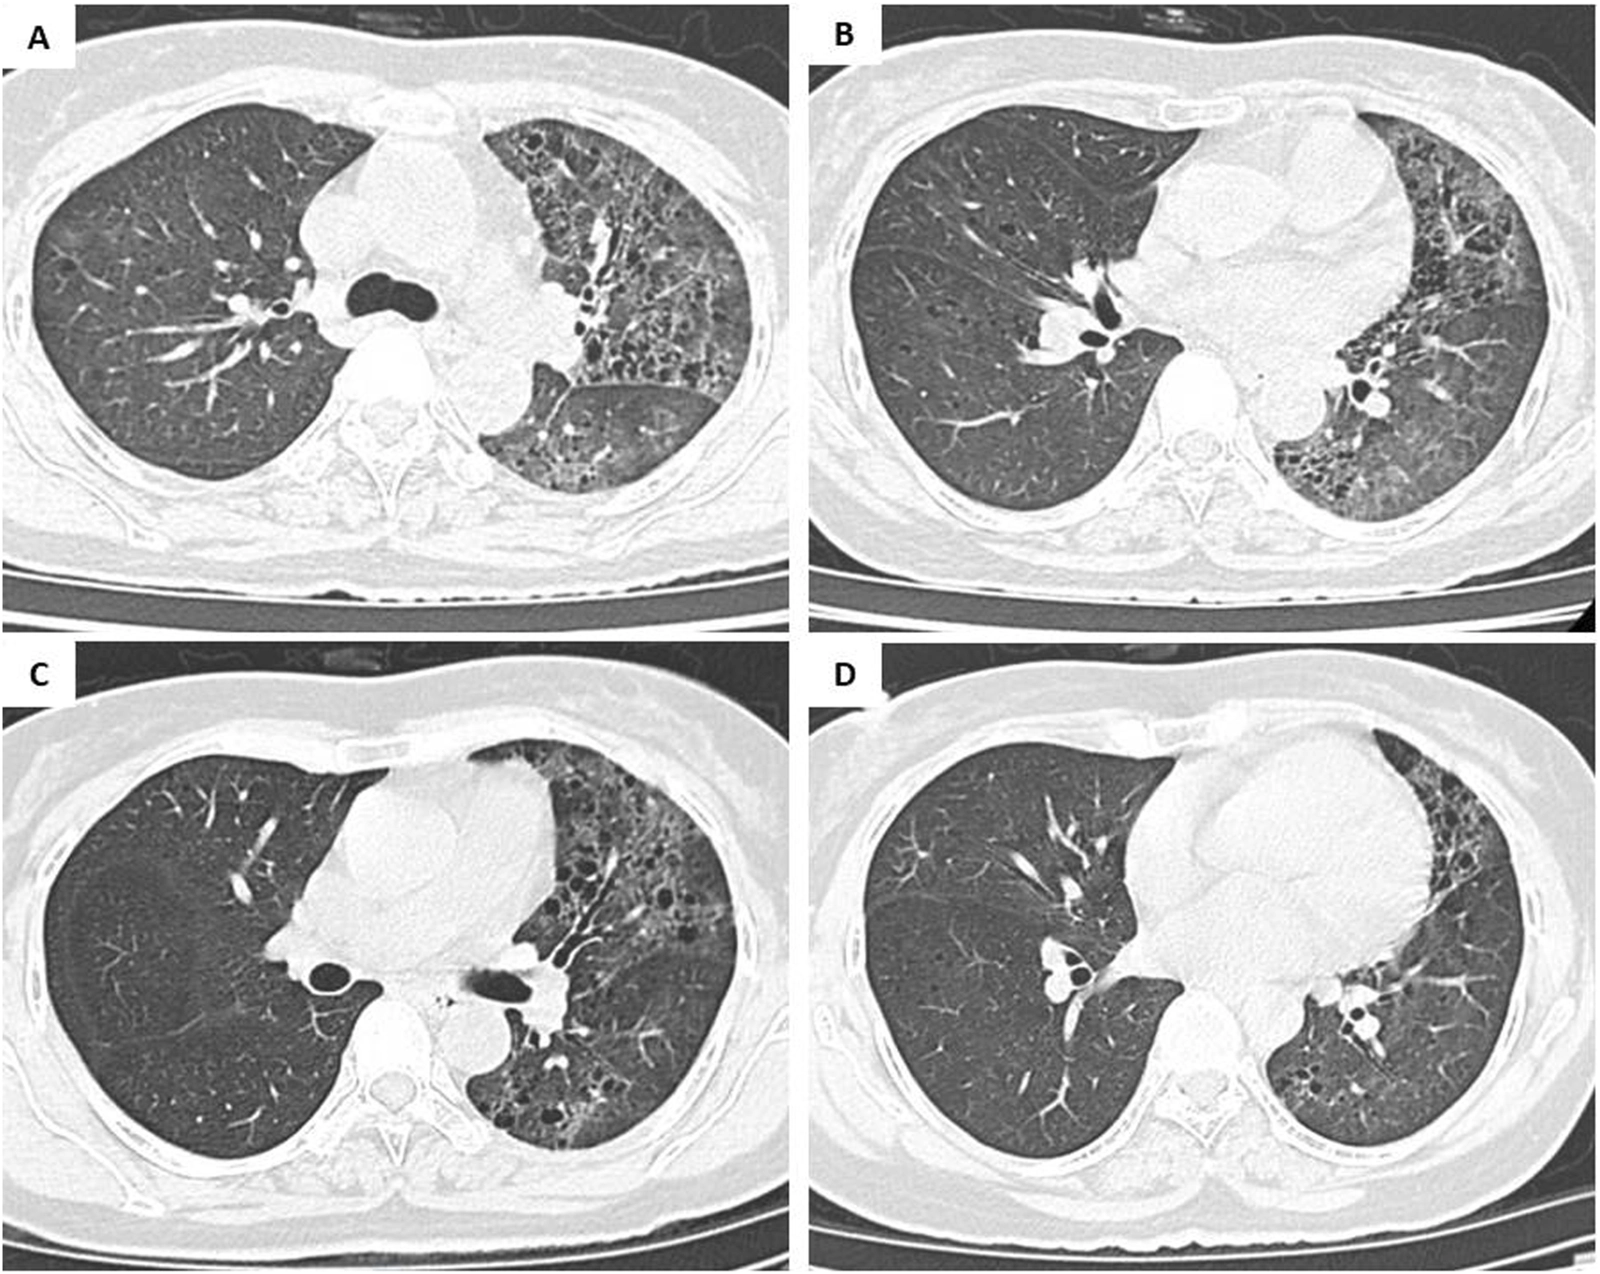

A 57-year-old, non-smoker, female patient presented with a persistent cough and sputum expectoration lasting for 3 months. Her medical history was unremarkable with no significant environmental or occupational exposure to carcinogens, and there was no known family history of lung cancer or other hereditary malignancies. Written informed consent was obtained from the patient for the publication of this case report and the associated clinical and genomic data. On 27th July 2023, she was admitted with a high volume of sputum production being recorded (>500 mL per day). On admission, the tuberculosis check-ups involving acid-fast bacillus (AFB) (2 samples), bronchoalveolar lavage, sputum gene Xpert, and Interferon Gamma Release Assay (IGRA) showed no abnormalities. The bronchoscopy also did not find any suspected lesion. On the chest computed tomography (CT), there was an alveolar condensation syndrome with an air bronchogram, scattered ground-glass opacities, and multiple nodular lesions in the left lung and the lower lobe of the right lung (shown in Figures 1A,B). However, the patient’s symptoms persisted despite antibiotic treatment. On 11 August 2023, she was referred for suspected AFB-negative pulmonary tuberculosis and received a 10-day anti-tuberculosis regimen, but the disease progressed, necessitating oxygen therapy at 3L/minute. By August 30th, she developed fever and bilateral crackles, with laboratory results showing a high white blood cell count (30 × 103/µL) and a CT scan confirming increased bilateral pulmonary lesions (shown in Figures 1C,D).

FIGURE 1

Within 2 days, her condition worsened to acute respiratory failure, characterized by tachypnea (30 breaths/min), grade 4 dyspnea, SpO2 dropping to 75%–85%, and requiring escalation of oxygen support to 10–15 L/min via continuous positive airway pressure (CPAP).